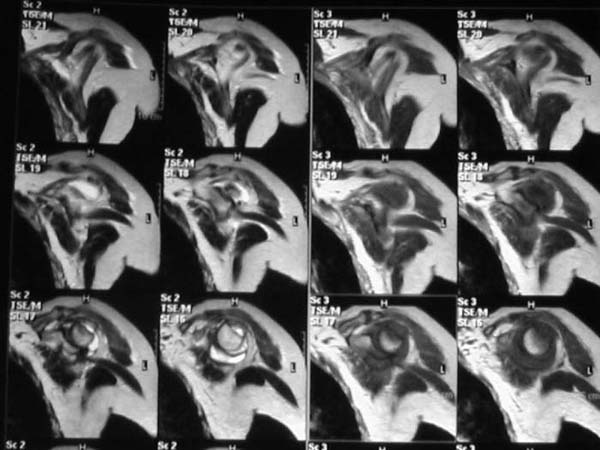

Из того, что видно на недостаточно качественно отсканированных МРТ - нижний подвывих плеча и синовиит. Непонятный очаг по заднему контуру головки плеча (то ли артефакт, то ли косой срез, проходящий между головкой и большим бугорком). Сухожилия вращательной манжетки выглядят целыми. Неправильная форма нижней части labrum glenoidale - разрыв ?

И еще одно пожелание - МРТ костно-суставной системы ОБЯЗАТЕЛЬНО нужно проводить с использованием сканов с подавлением сигнала от жировой ткани (SPIR - на Филипсах, у Вас, как я вижу - Филипс; FATSAT - на других томографах, либо STIR - есть на любых аппаратах). Только так можно увидеть отек мягких тканей и костного мозга на фоне жировой ткани.

Плоскости при сканировании плеча обязательно должно быть 3

1. Ортогональная поперечная (аксиальная)

2. Косая корональная (параллельно длинной оси диафиза)

2. Косая сагиттальная (так же параллельно диафизу плеча)

МРТ должен показать разрыв манжетки, но признаться я не большой эксперт по чтению МРТ сканов, хотя затемнение, отек мягких тканей по задней поверхности плеча видны Обычные рентгенограммы демонстрируют остеолизис в области большого бугорка.

В приложенном файле - МРТ изображение. Более информативно, чем предыдущий вариант? менее? или также?

Все-таки, должен признать, что такие снимки - суррогат. Информативность чуть-чуть лучше, за счет большего размера. С учетом сложных топографо-анатомических соотношений необходимо иметь картину всех срезов, и смотреть их поочередно, иначе не создается целостной картины, а также иметь возможность манипулировать контрастом. Вот если б снимки были в DICOME - тогда от интерпретации было бы не отвертеться -)

1. На рентгене - нижний подвывих плеча и очаг остеолиза суставного бугорка с четкими контурами (вдавленный перелом на фоне остеопороза ? доброкачественная опухоль? аваскулярный некроз ? (хотя ни разу не слышал об аваскулярном некрозе плеча..)

2.выраженный выпот в полости сустава

3. Сказать о связках и сухожилиях что-то при снимках в таком режиме не берусь.